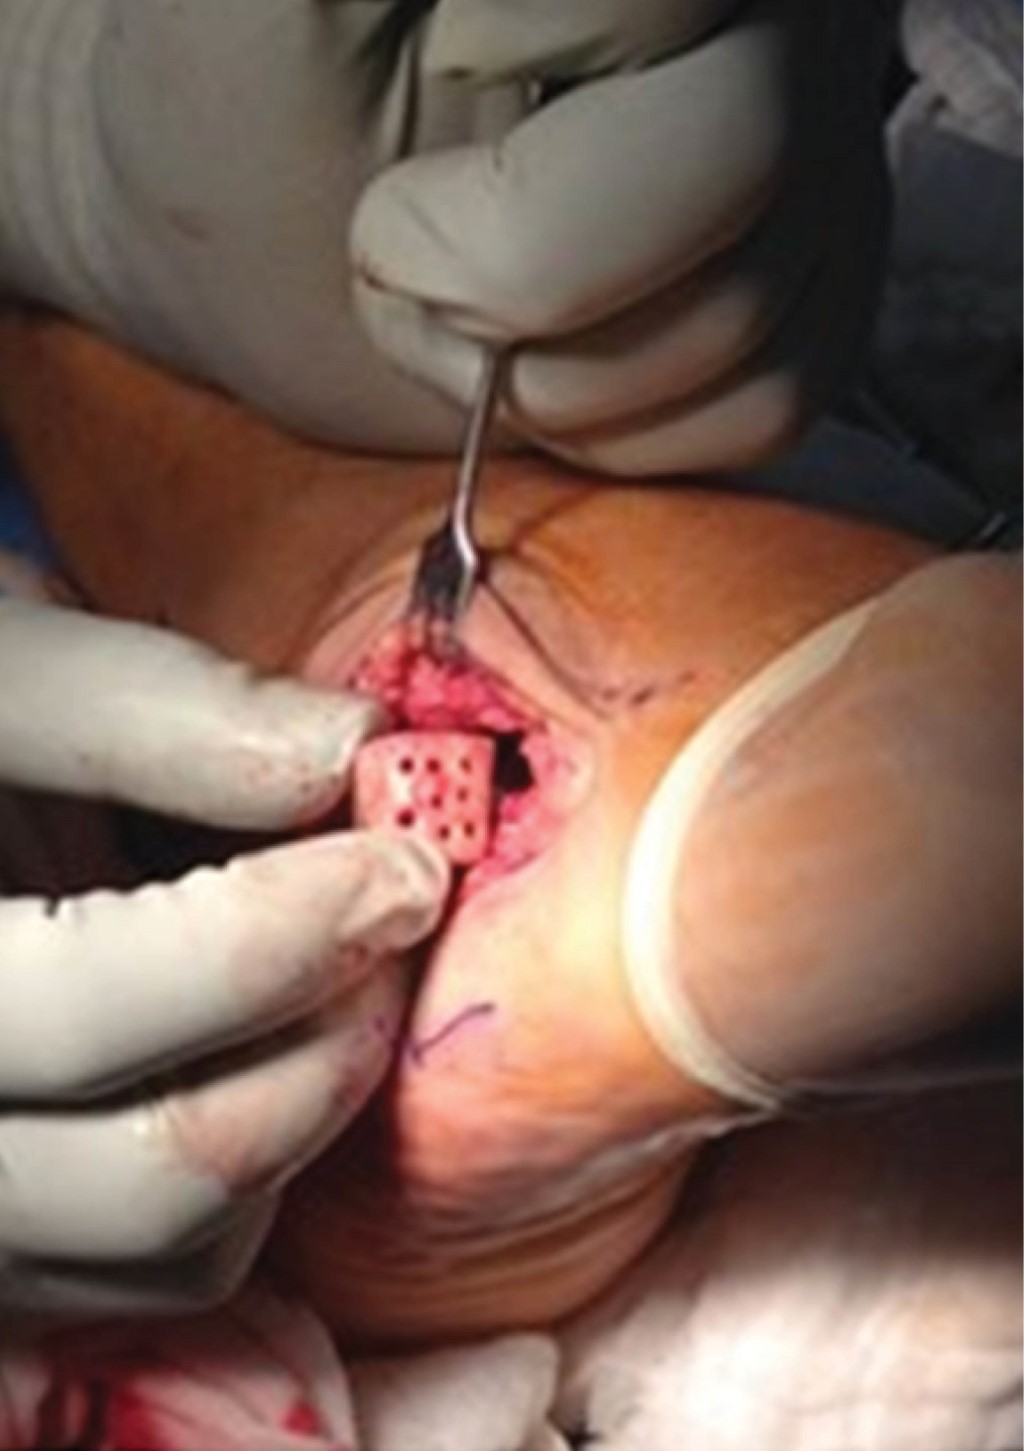

Se realizó la biopsia transquirúrgica, la cual reveló abundante tejido fibroconectivo con osteoblastos y nidos de hueso trabecular con matriz ósea y tejido osteoide e hipervascularidad del estroma, aumento de la celularidad sin atipias y escasas células gigantes multinucleadas (Figura 4); se clasificó como Enneking 2. Se inició tratamiento con resección y curetaje del tumor, crioterapia y colocación de injerto tricortical en el defecto en cuboides (Figura 5).